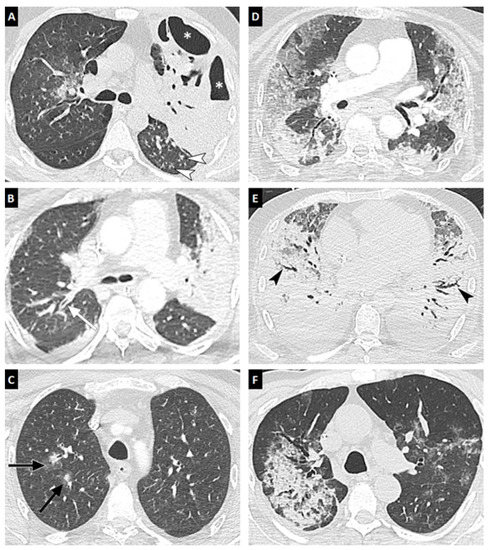

| All Aspergillosis Patients (n = 24) | IAPA (n = 14) | CAPA (n = 10) | p Value | |

|---|---|---|---|---|

| Delay between ICU admission and CT scan | 10 (4–15) | 9 (4–15) | 10 (3–15) | 0.99 |

| Delay between IPA diagnosis and CT scan | 5 (0–9) | 4 (0–9) | 7 (0–9) | 0.75 |

| Diffuse reticular or alveolar opacities | 24 (100%) | 14 (100%) | 10 (100%) | 0.99 |

| Wedge-shaped segmental or lobar consolidation | 17 (70.8%) | 10 (71.4%) | 7 (70.0%) | 0.99 |

| Well-circumscribed nodule(s) | 6 (25.0%) | 6 (42.9%) | 0 (0.0%) | 0.024 |

| Halo sign | 3 (12.5%) | 2 (14.3%) | 1 (10.0%) | 0.68 |

| Cavitation | 5 (20.8%) | 5 (35.7%) | 0 (0.0%) | 0.053 |

| Air-crescent sign | 0 (0.0%) | 0 (0.0%) | 0 (0.0%) | 0.99 |

| Tree in bud | 7 (29.2%) | 7 (50.0%) | 0 (0.0%) | 0.019 |

| Bronchial wall thickening | 8 (33.3%) | 8 (57.1%) | 1 (10.0%) | 0.03 |

| Pleural effusion | 9 (37.5%) | 5 (35.7%) | 4 (40.0%) | 0.99 |